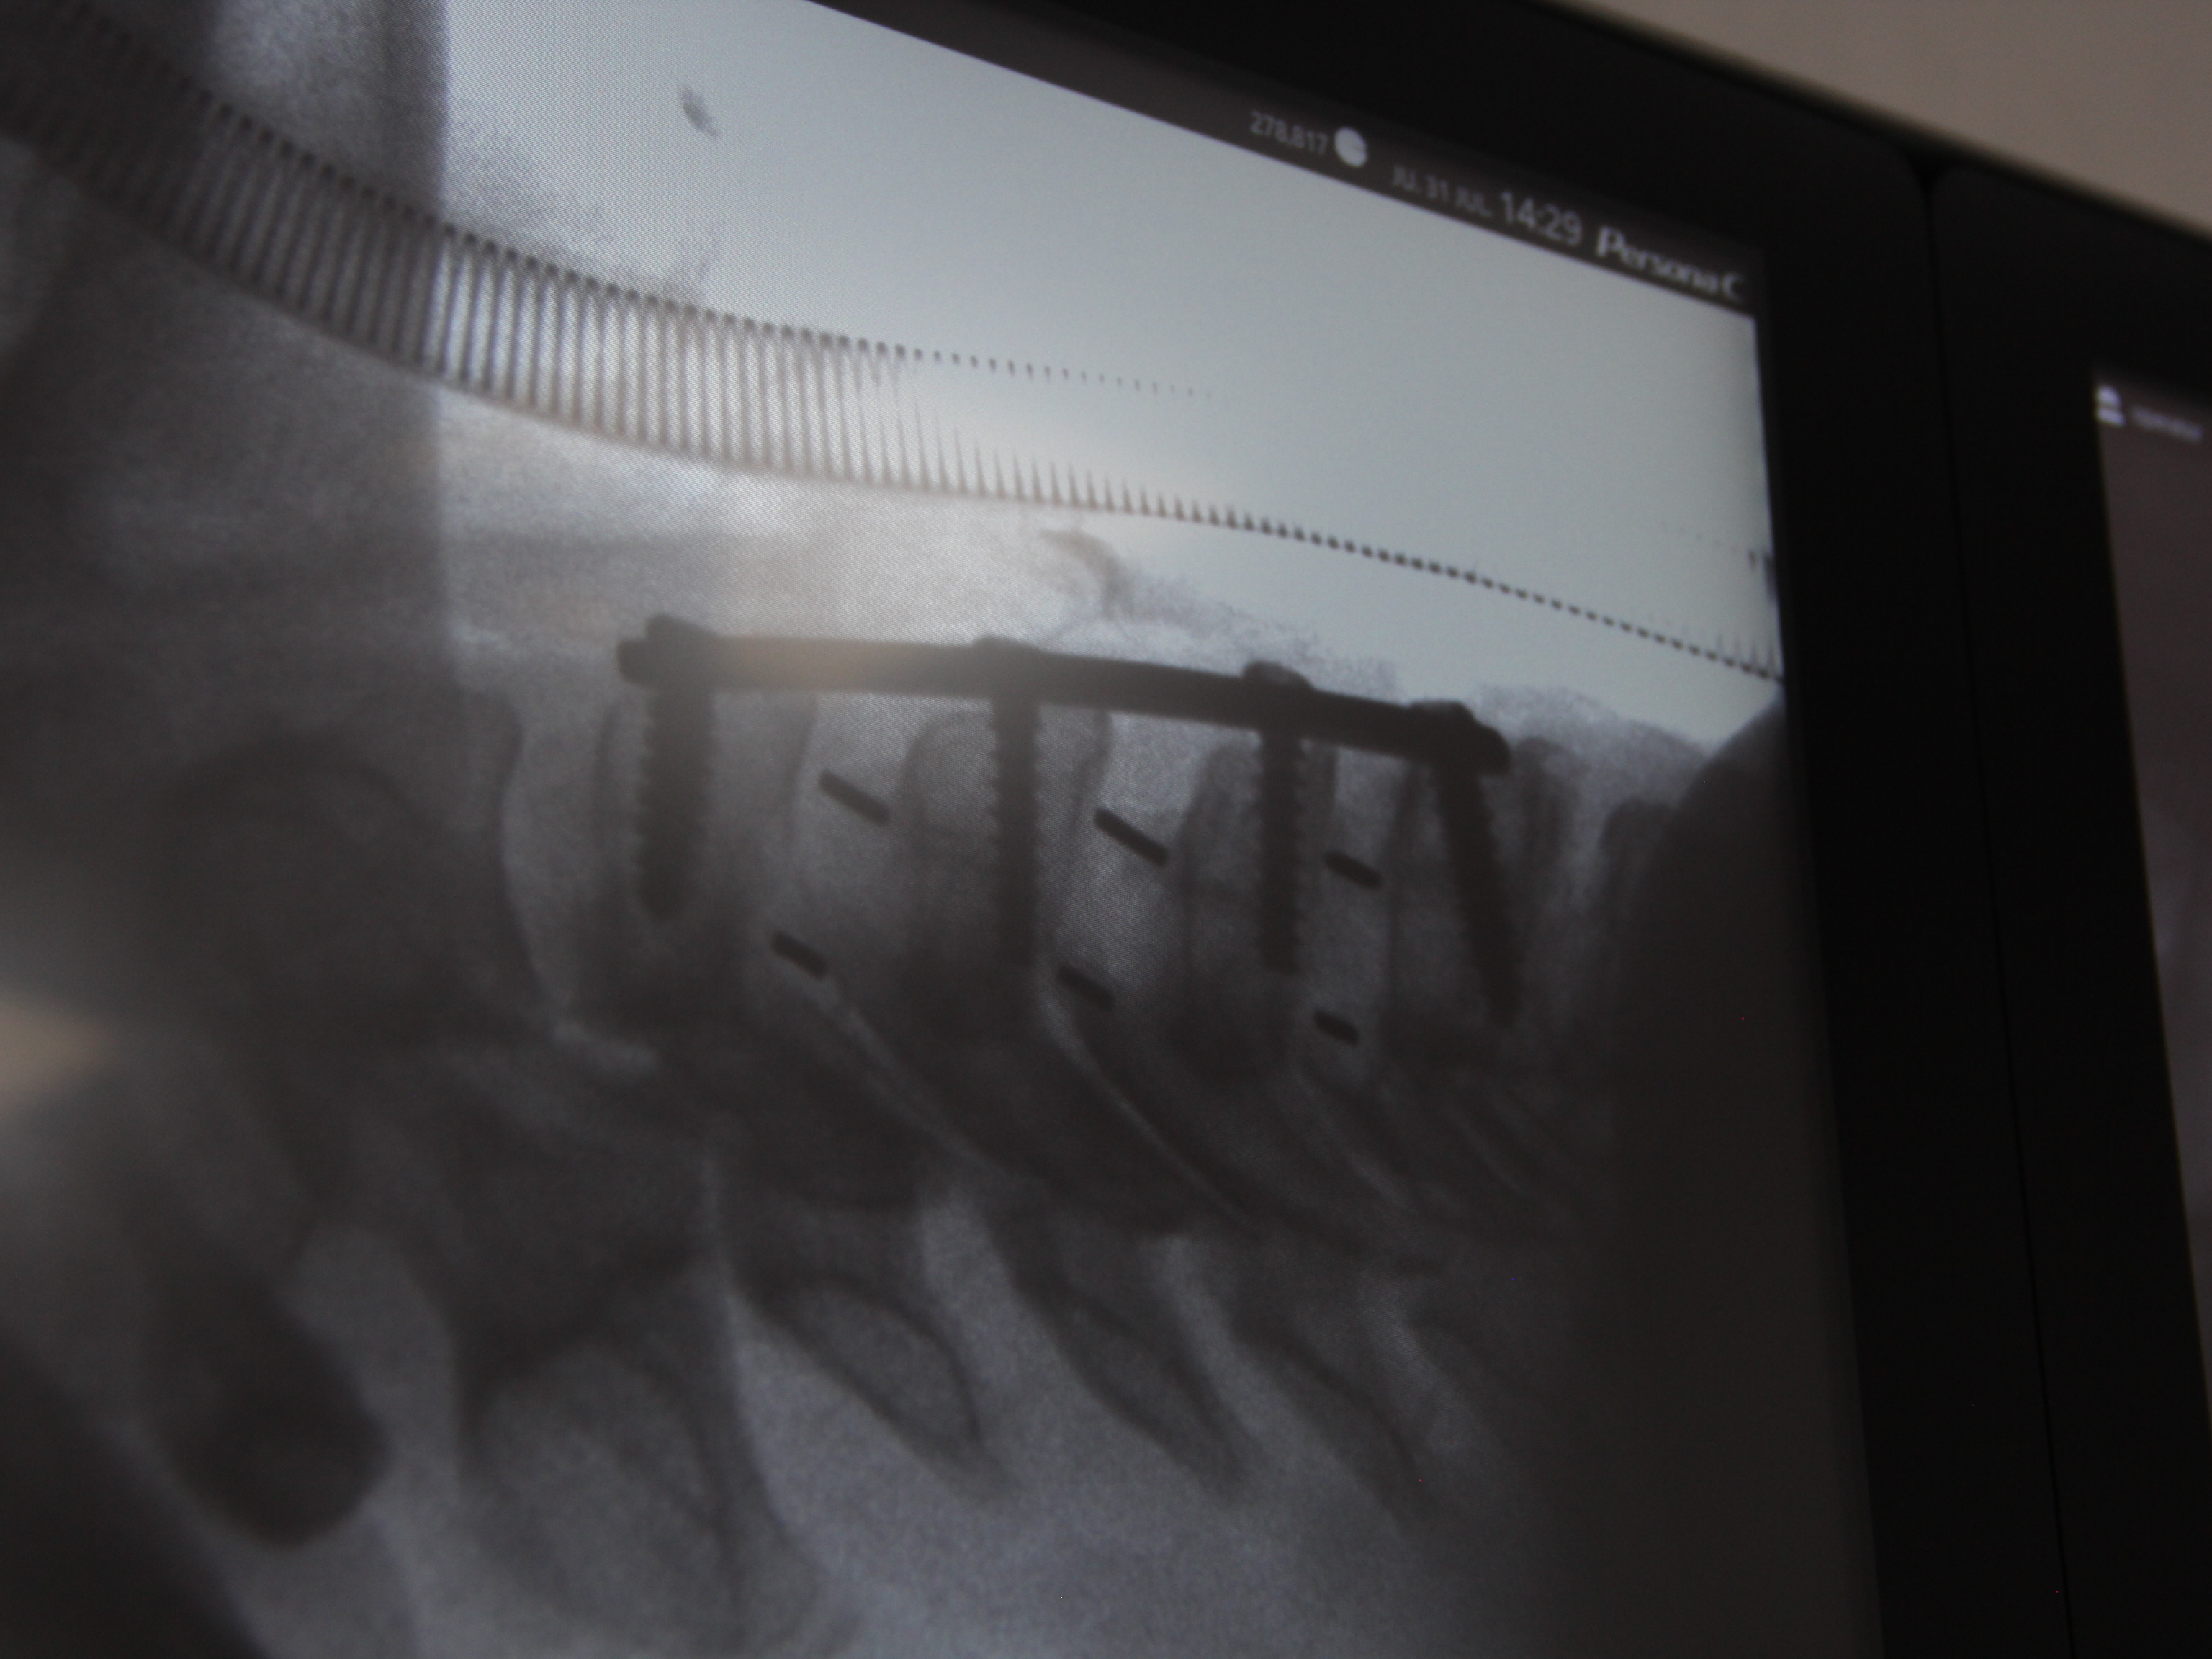

Cada procedimiento requiere una planificación detallada, basada en estudios de imagen y evaluación clínica, con el objetivo de lograr una descompresión adecuada de estructuras nerviosas y restaurar la estabilidad vertebral.

Se emplean técnicas quirúrgicas modernas, incluyendo abordajes mínimamente invasivos cuando son viables, lo que permite una recuperación más rápida y menor impacto en el paciente.